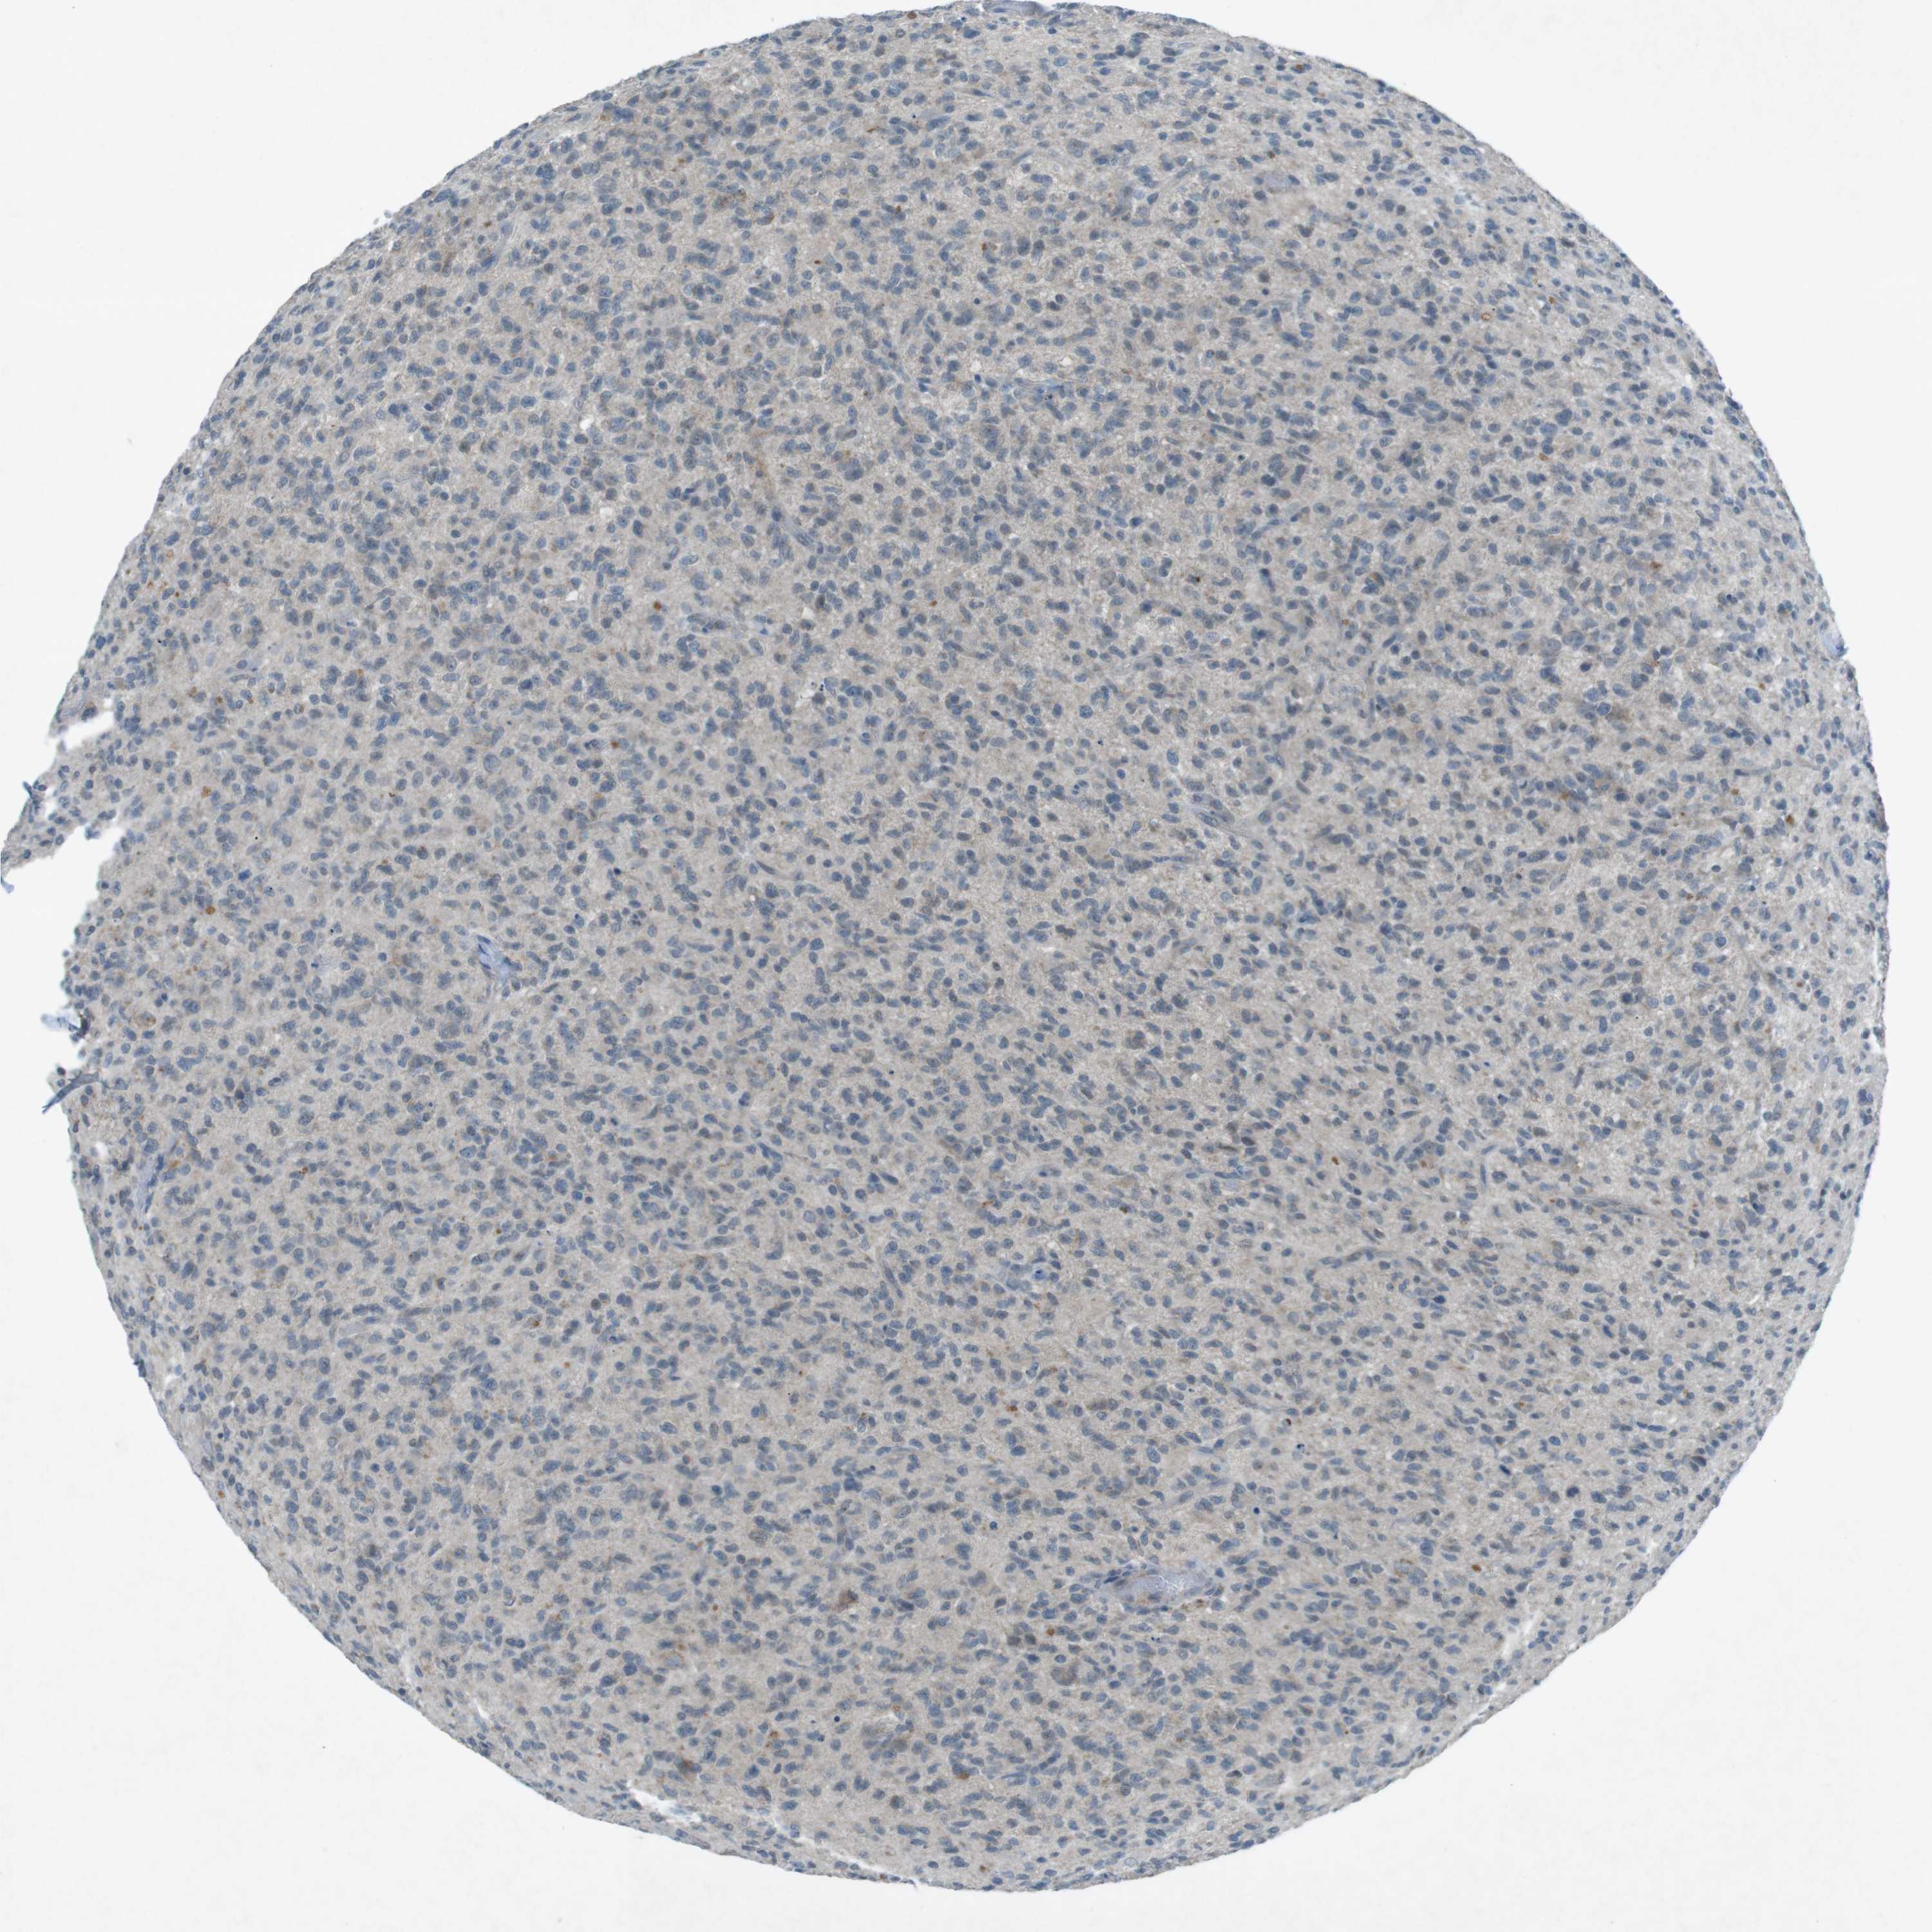

GLIOMA - Protein expressioni

A mouse-over function shows sample information and annotation data. Click on an image to view it in a full screen mode. Samples can be filtered based on level of antibody staining by selecting one or several of the following categories: high, medium, low and not detected. The assay and annotation is described here.

Note that samples used for immunohistochemistry by the Human Protein Atlas do not correspond to samples in the TCGA dataset.

Antibody stainingi

Antibody staining in the annotated cell types in the current human tissue is reported as not detected, low, medium, or high, based on conventional immunohistochemistry profiling in selected tissues. This score is based on the combination of the staining intensity and fraction of stained cells.

Each image is clickable and will lead to virtual microscopy that enables deeper exploration of all samples and also displays staining intensity scores, fraction scores and subcellular localization as well as patient and tissue information for each sample.

Antibody CAB016545

Staining

High

Medium

Low

Not detected

Intensity

Strong

Moderate

Weak

Negative

Quantity

>75%

75%-25%

<25%

None

Location

Nuclear

Cytoplasmic/membranous

Cytoplasmic/membranous,nuclear

Glioma, malignant, High grade

Glioma, malignant, Low grade